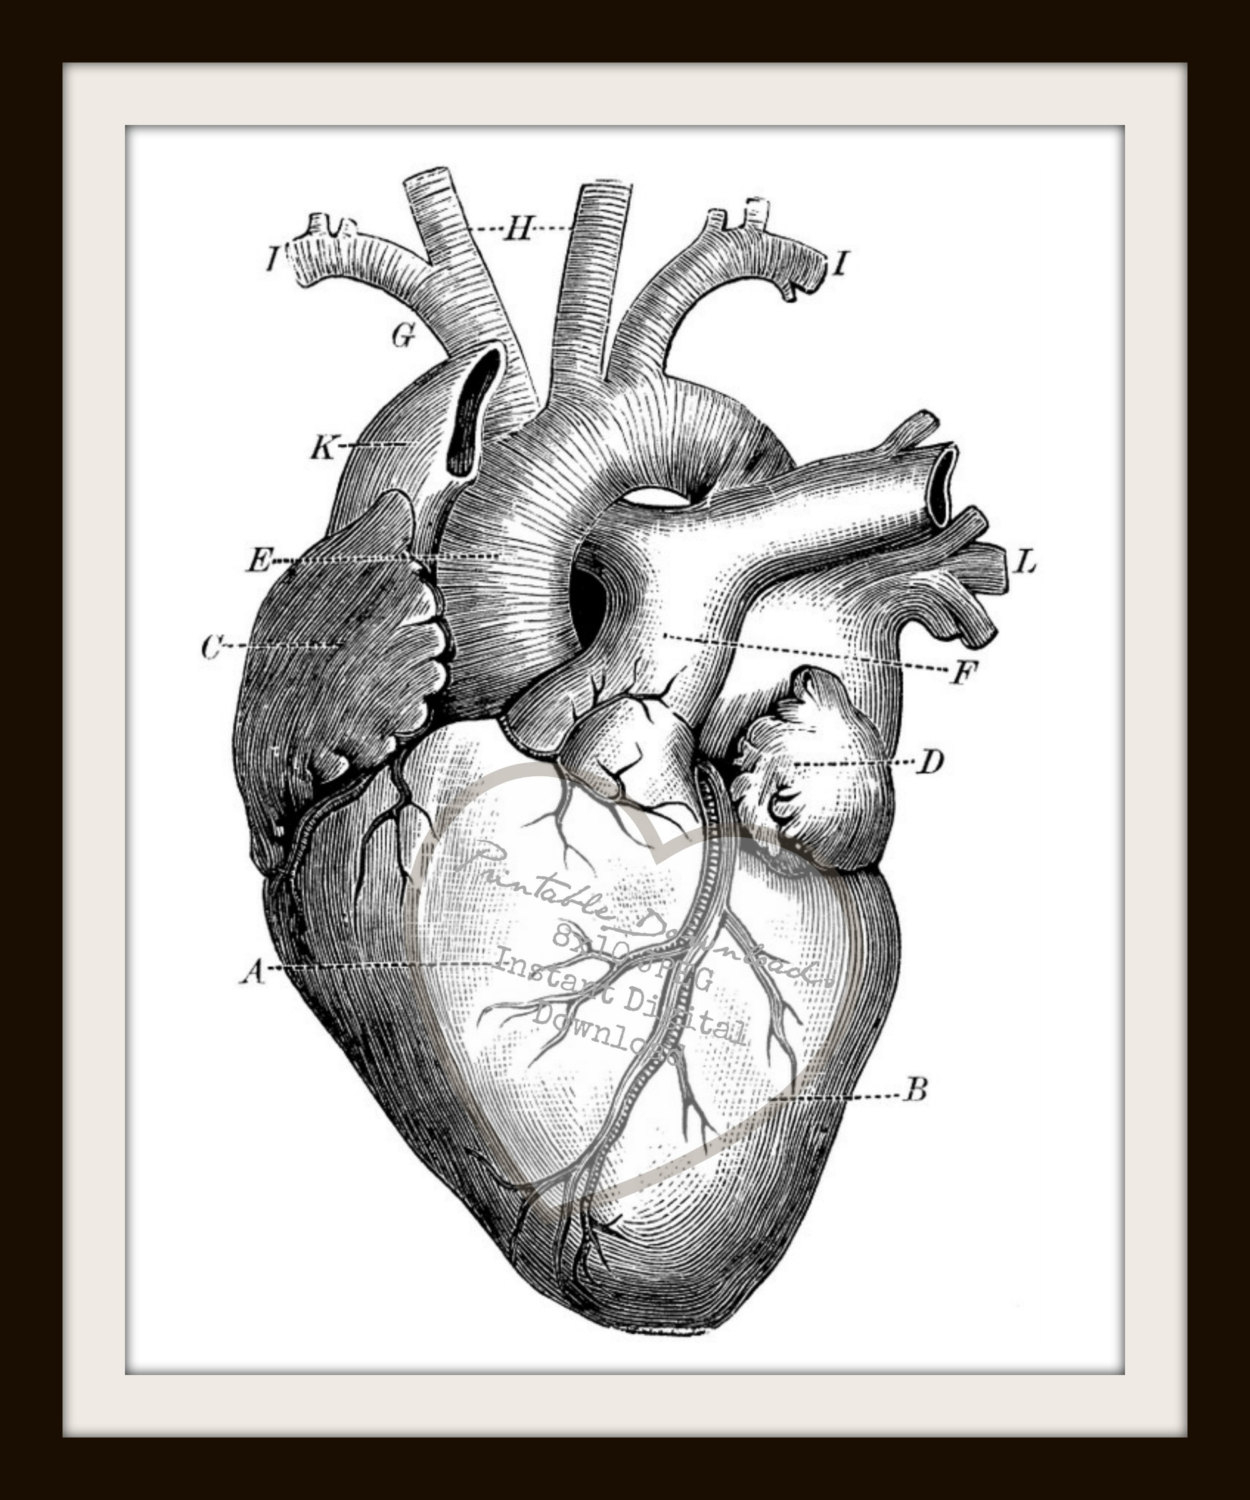

Anatomical Heart Drawing at GetDrawings | Free download  Detailed 3D Human Heart | CGTrader

How to Draw a Heart - Science Drawing Lesson | Heart drawing, Anatomical heart drawing, Human  Realistic Heart Drawing 1000 Ideas About Human Heart On Pinterest Anatomical Heart | Heart

Sketch Human Heart Diagram Labeled - fallinlovewithyou-raura  Human Heart Anatomy 1 3D model | CGTrader

How the Human Heart Works | Safety and Health Solutions  3d human heart